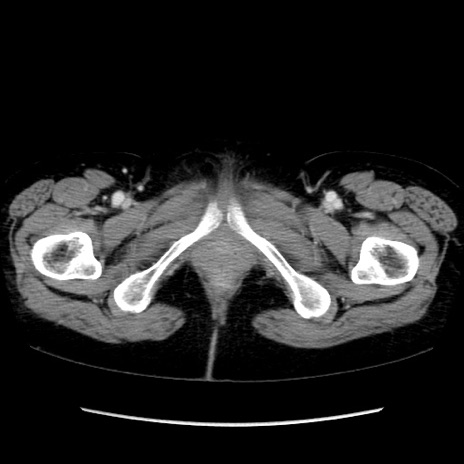

【症例】40歳代 女性

【主訴】上腹部痛、嘔気・嘔吐

【現病歴】約9時間前頃から急に上腹部痛、嘔気、嘔吐が出現。改善しないため救急要請。

【既往歴】子宮頚癌(広汎子宮全摘術、放射線療法)、腸閉塞

【身体所見】腹部:平坦、軟、腸雑音亢進、上腹部を中心に腹部全体に圧痛あり。

【データ】WBC 8400、CRP 0.03